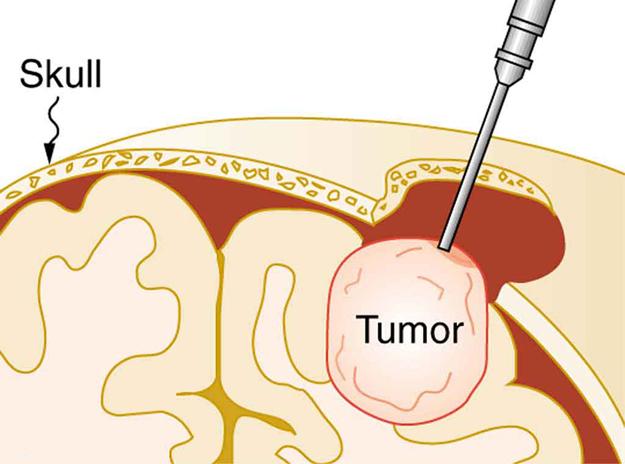

Ultrasound, like any wave, carries energy that can be absorbed by the medium carrying it, producing effects that vary with intensity. When focused to intensities of to , ultrasound can be used to shatter gallstones or pulverize cancerous tissue in surgical procedures. (See Figure 17.45.) Intensities this great can damage individual cells, variously causing their protoplasm to stream inside them, altering their permeability, or rupturing their walls through cavitation. Cavitation is the creation of vapor cavities in a fluid—the longitudinal vibrations in ultrasound alternatively compress and expand the medium, and at sufficient amplitudes the expansion separates molecules. Most cavitation damage is done when the cavities collapse, producing even greater shock pressures.